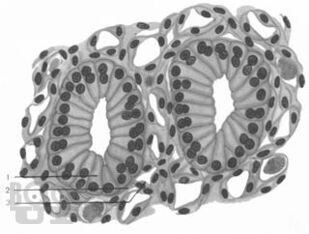

Учебное пособие предназначено для самостоятельной работы с микропрепаратами при подготовке к итоговым практическим занятиям по общему и частному курсу гистологии студентов I и II курсов лечебного и педиатрического факультетов.